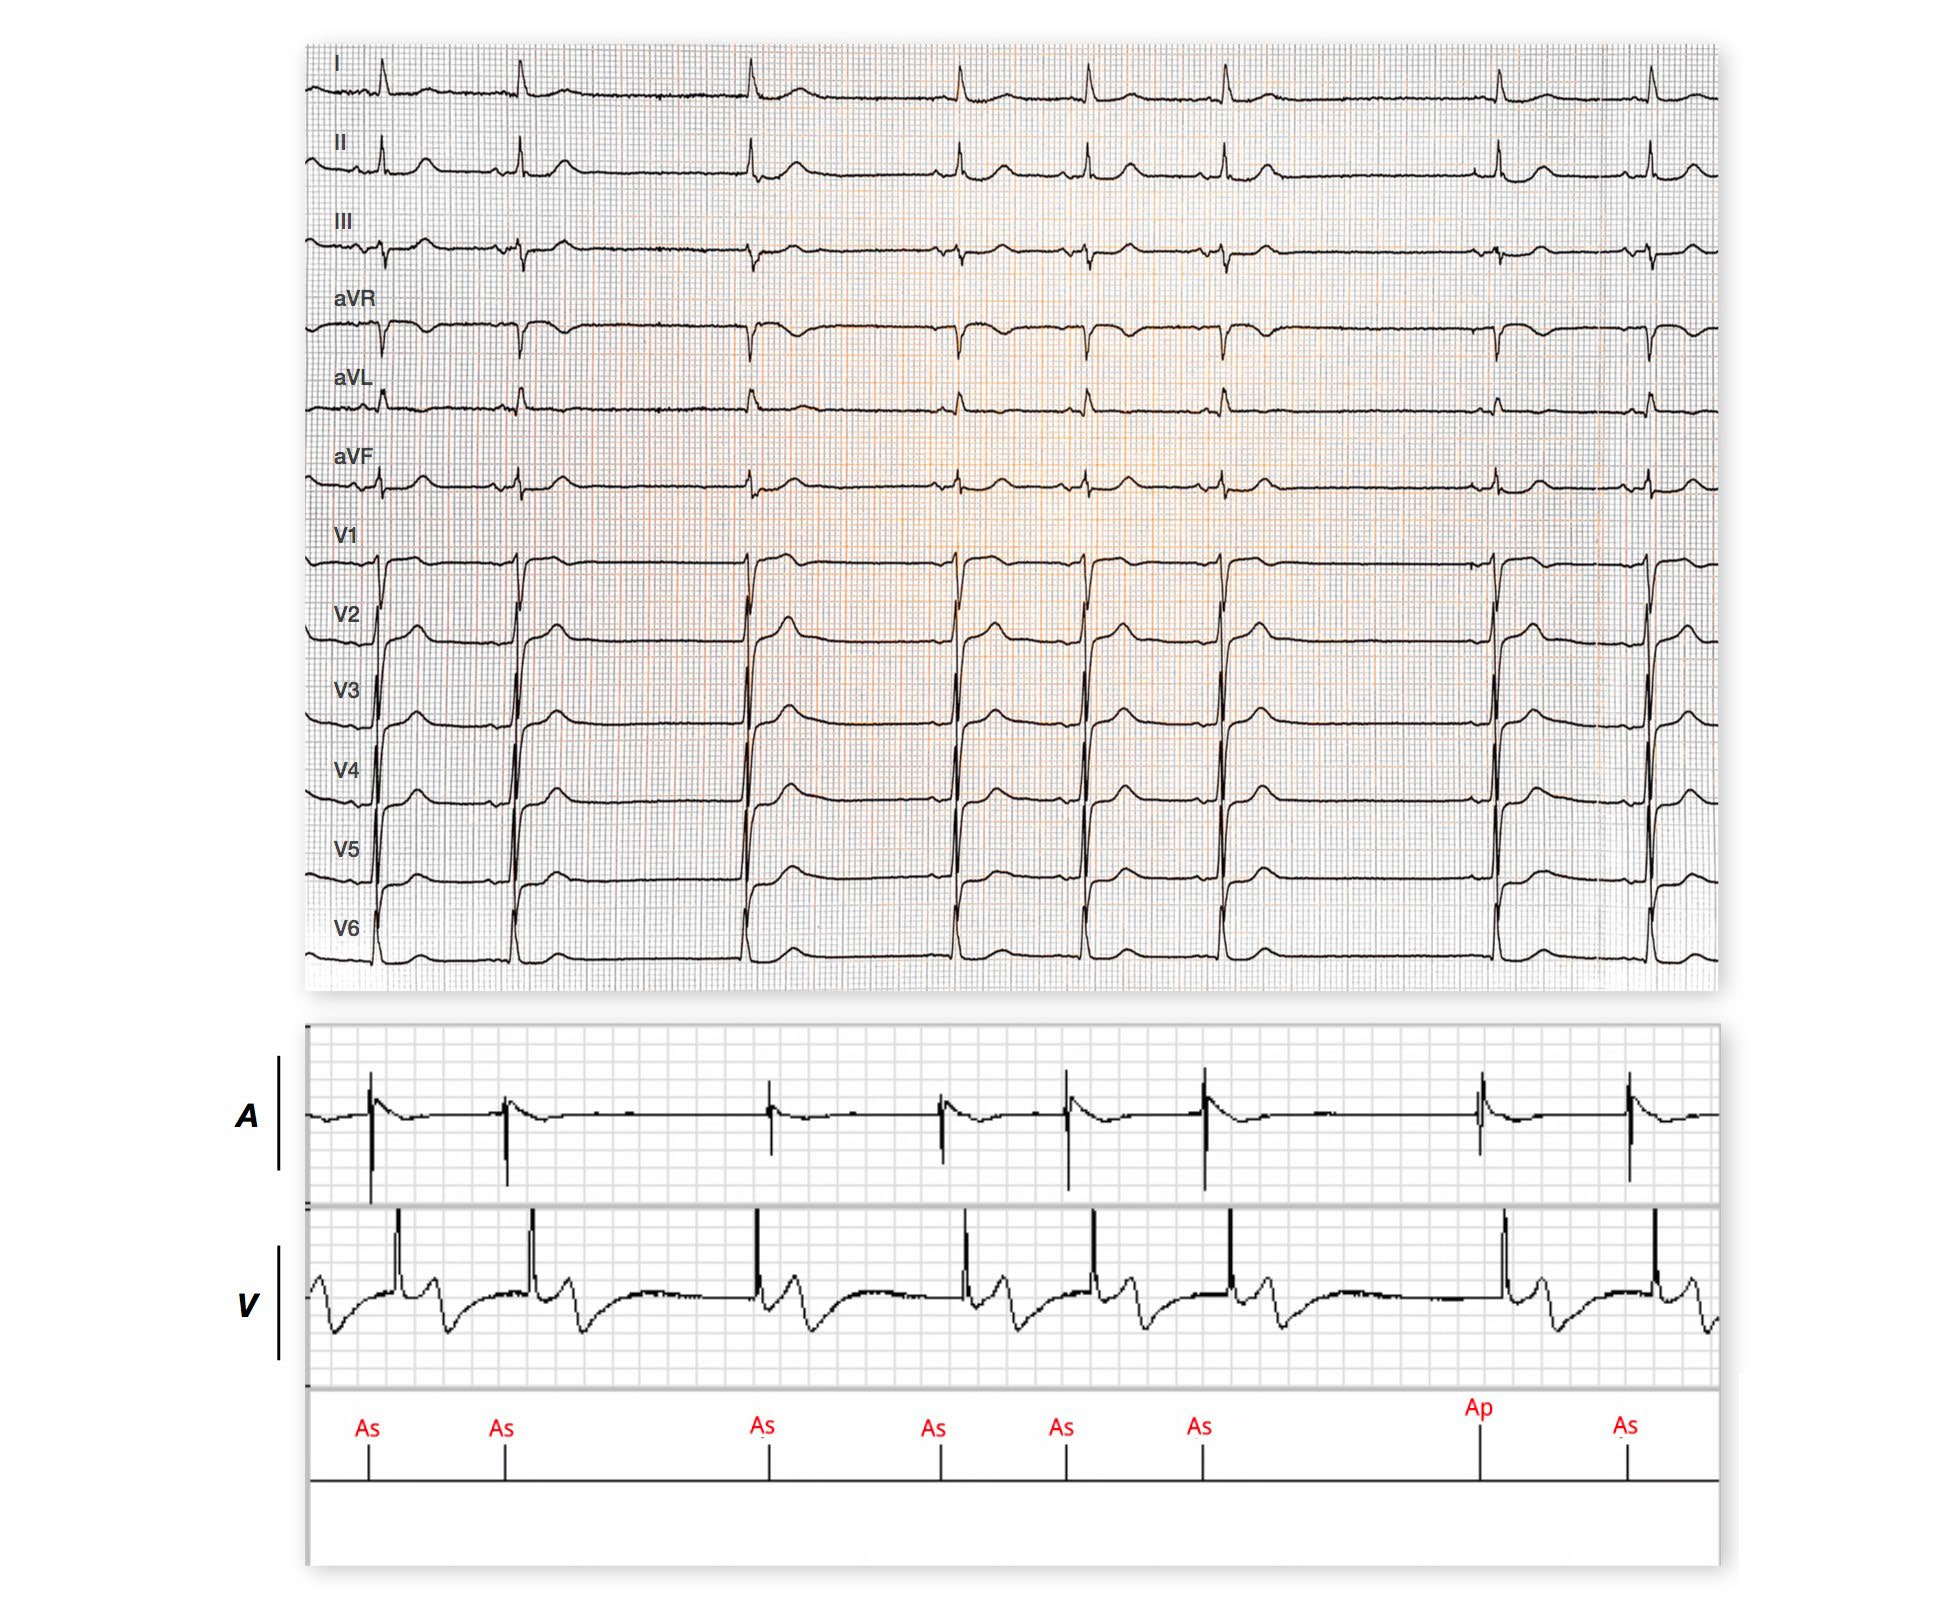

AAI mode 30 beats/minute: initially, sinus activity (P) is faster than the minimum rate; first sinus pause with junctional escape; second pause with atrial pacing (Ap) after 2 seconds which corresponds to the minimum rate;

A single-chamber pacemaker operates in AAI mode when only one lead is positioned in the atrium; AAI mode can also be programmed in a dual-chamber pacemaker. These tracings allow to highlight the main characteristics of this pacing mode: • sensing and pacing of the atrium, inhibition on an intrinsic atrial event; the preferred indication is therefore pure sinus dysfunction without ventricular conduction disorder. An AAI pacemaker allows 1) to limit the number of implanted leads, 2) to ensure a physiological rate both at rest and during exercise after programming the rate response function and 3) to avoid any unnecessary ventricular pacing. • absence of ventricular sensing or pacing. Single-chamber AAI pacemakers or AAI mode programming on a dual-chamber pacemaker are formally contraindicated in patients with permanent or paroxysmal atrioventricular conduction disorder. Similarly, it is preferable not to use the AAI mode in instances of long PR interval, intraventricular conductive disorder, low Luciani-Wenckebach point, long HV. This mode should also be avoided in patients with vagal symptoms or carotid sinus syndrome. When the pacemaker operates in AAI mode, it may be necessary to program operation; indeed, the amplitude of the atrial complexes is most often weaker period may be programmed longer to prevent ventricular oversensing by the a decrease in the pacing rate, because each sensed R wave recycles the escape possible to lower the sensitivity of the pacemaker and/or to prolong 3344